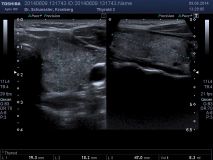

Farbkodierte Ultraschalluntersuchung der Schilddrüse

Mit dieser Untersuchung lassen sich die Schilddrüsengröße, ihre Struktur und auch Knoten, Zysten oder entzündliche Veränderungen sichtbar machen. Durch Hinzunahme der Farbkodierung lässt sich auch die Durchblutungssituation der Schilddrüse sichtbar machen.

Ultraschalluntersuchung am liegenden Patienten.

Dauer: Je nach Fragestellung mehrere Minuten.